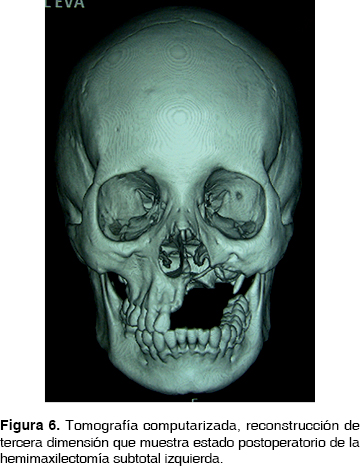

Se inicia manejo con clindamicina 600 mg IV cada 8 h y ceftriaxona 1 g IV cada 12 h. A continuación, bajo anestesia general inhalatoria balanceada, se realiza hemimaxilectomía subtotal, mediante abordaje circunvestibular durante el procedimiento se observan áreas óseas líticas y necróticas (Figura 4) , se procede a la resección de la lesión obteniendo un espécimen quirúrgico de 2 x 4 cm. Se sutura con ácido poliglicólico 3 ceros. Se envía la pieza quirúrgica a patólogo oral que reporta osteomielitis crónica maxilar con bordes libres de lesión, continúa durante 30 días con penicilina G procaínica 800,000 UI IM cada 24 h por 30 días. En la actualidad se encuentra clínica e imagenológicamente sin datos de recidiva (Figuras 5 y 6).